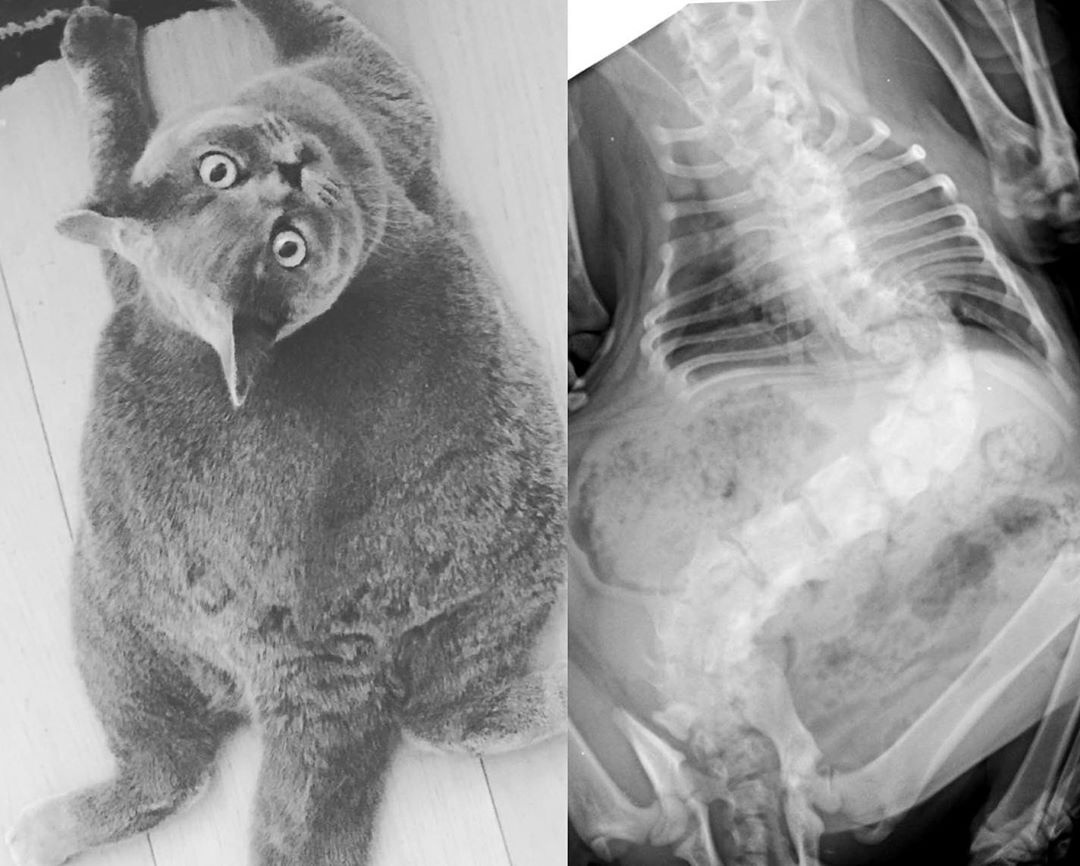

Từng bị chủ bỏ rơi vì bị vẹo cột sống, sức khỏe kém, chú mèo tên Pitoe may mắn tìm được gia đình mới yêu thương và nổi tiếng trên mạng nhờ vẻ ngoài đáng yêu.

Gương mặt lúc nào cũng ngơ ngác, thân hình mũm mĩm, tròn như quả bóng là nhận xét chung của nhiều người khi nhìn thấy loạt ảnh về chú mèo tên Pitoe (4 tuổi). Bên cạnh nhiều bình luận khen đáng yêu, không ít người bày tỏ sự lo ngại cho sức khỏe Pitoe, sợ chú bị béo phì do ăn uống quá độ. Tuy nhiên, một trong những lý do khiến Pitoe có vẻ ngoài như vậy là căn bệnh vẹo cột sống hiếm gặp ở mèo.

Chú mèo 4 tuổi thuộc giống mèo Anh lông ngắn được gia đình của Marie nhận nuôi cách đây không lâu. "Vì Pitoe bị vẹo cột sống khá nghiêm trọng nên cơ thể của nó ngắn hơn nhiều so với những con mèo bình thường. Bố mẹ tôi là bác sĩ thú y. Một ngày nọ, họ phát hiện Pitoe sắp bị một người bán mèo bỏ rơi vì vẻ ngoài xấu nên quyết định nhận nuôi", Marie nói với Bored Panda.

Ông bà Marie vốn là người rất thích mèo song trước đây không dám nhận nuôi vì sợ chúng có thể nhảy qua ban công bị thương hoặc làm phiền gia đình hàng xóm. "Nhưng Pitoe lại khác, chính vì bị vẹo cột sống, nó không thể nhảy lên cao mà chỉ có thể di chuyển loanh quanh. Vì vậy, bố mẹ tôi đã tặng lại Pitoe cho ông bà nuôi. Pitoe giống như một món quà dành cho gia đình tôi vậy", Marie chia sẻ.

Dù không thể nhảy lên cao, Pitoe vẫn có thể thực hiện các hoạt động khác như nhiều con mèo bình thường. Chú mèo 4 tuổi thường đi lại lạch bạch quanh nhà, chạy, chơi và leo trèo những nơi thấp khá giỏi.

"Nhiều người lo lắng Pitoe bị béo phì nhưng thực ra thân hình nó như vậy một phần do cột sống bị vẹo. Chúng tôi vẫn luôn cho nó kiểm tra sức khỏe thường xuyên và đảm bảo chế độ ăn lành mạnh. Nó cũng không gặp đau đớn gì", Marie cho biết.